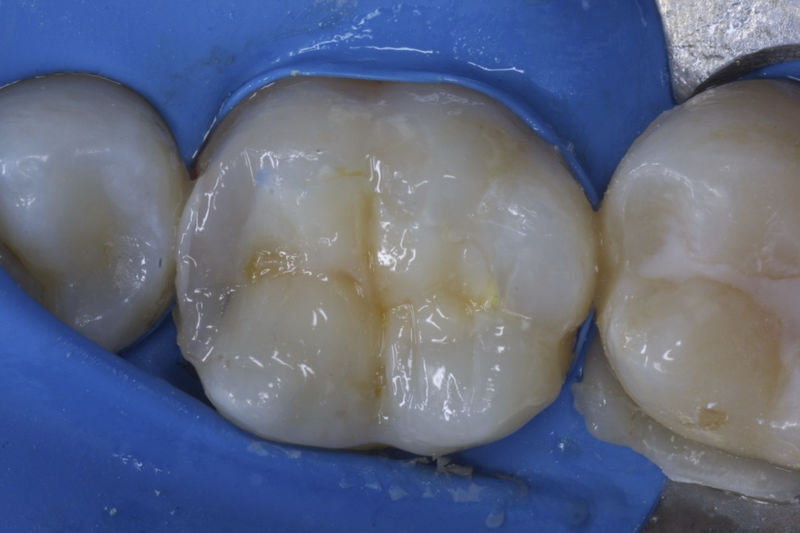

Restauraciones fabricadas en el laboratorio con materiales estéticos, los cuales cubren de manera parcial dientes posteriores. Se utilizan primariamente para restaurar dientes con caries, fracturas y/o defectos amplios. Para poder enviar el caso al laboratorio se toman impresiones utilizando materiales de impresión o técnicas modernas digitales.

Disciplina fundamental de la Odontología enfocada en el diagnóstico, prevención y tratamiento restaurador de las piezas dentales que han sufrido daños. Su objetivo principal es devolver al diente su equilibrio biológico, funcional y estético cuando su integridad ha sido alterada. Resinas directas, incrustaciones, coronas.

La restauración de un diente tras una endodoncia, es crucial para su supervivencia a largo plazo, ya que el procedimiento puede debilitar la estructura dental. El tipo de restauración elegido depende principalmente de la cantidad de estructura dental remanente después de la endodoncia. Principalmente se usan incrustaciones, coronas y/o postes.